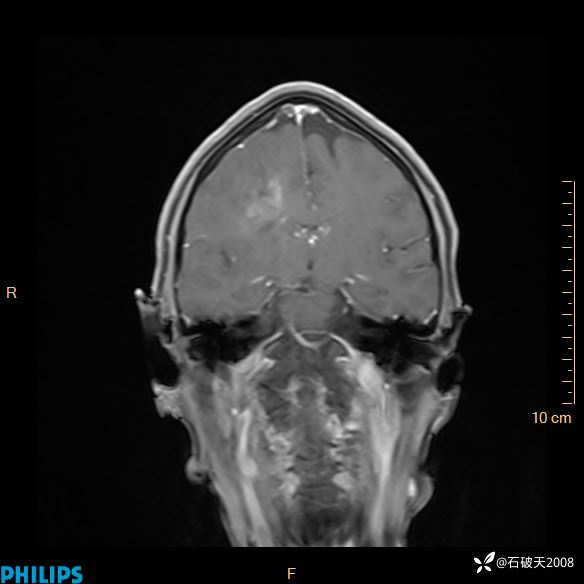

2024.2.21MR

增强冠状位